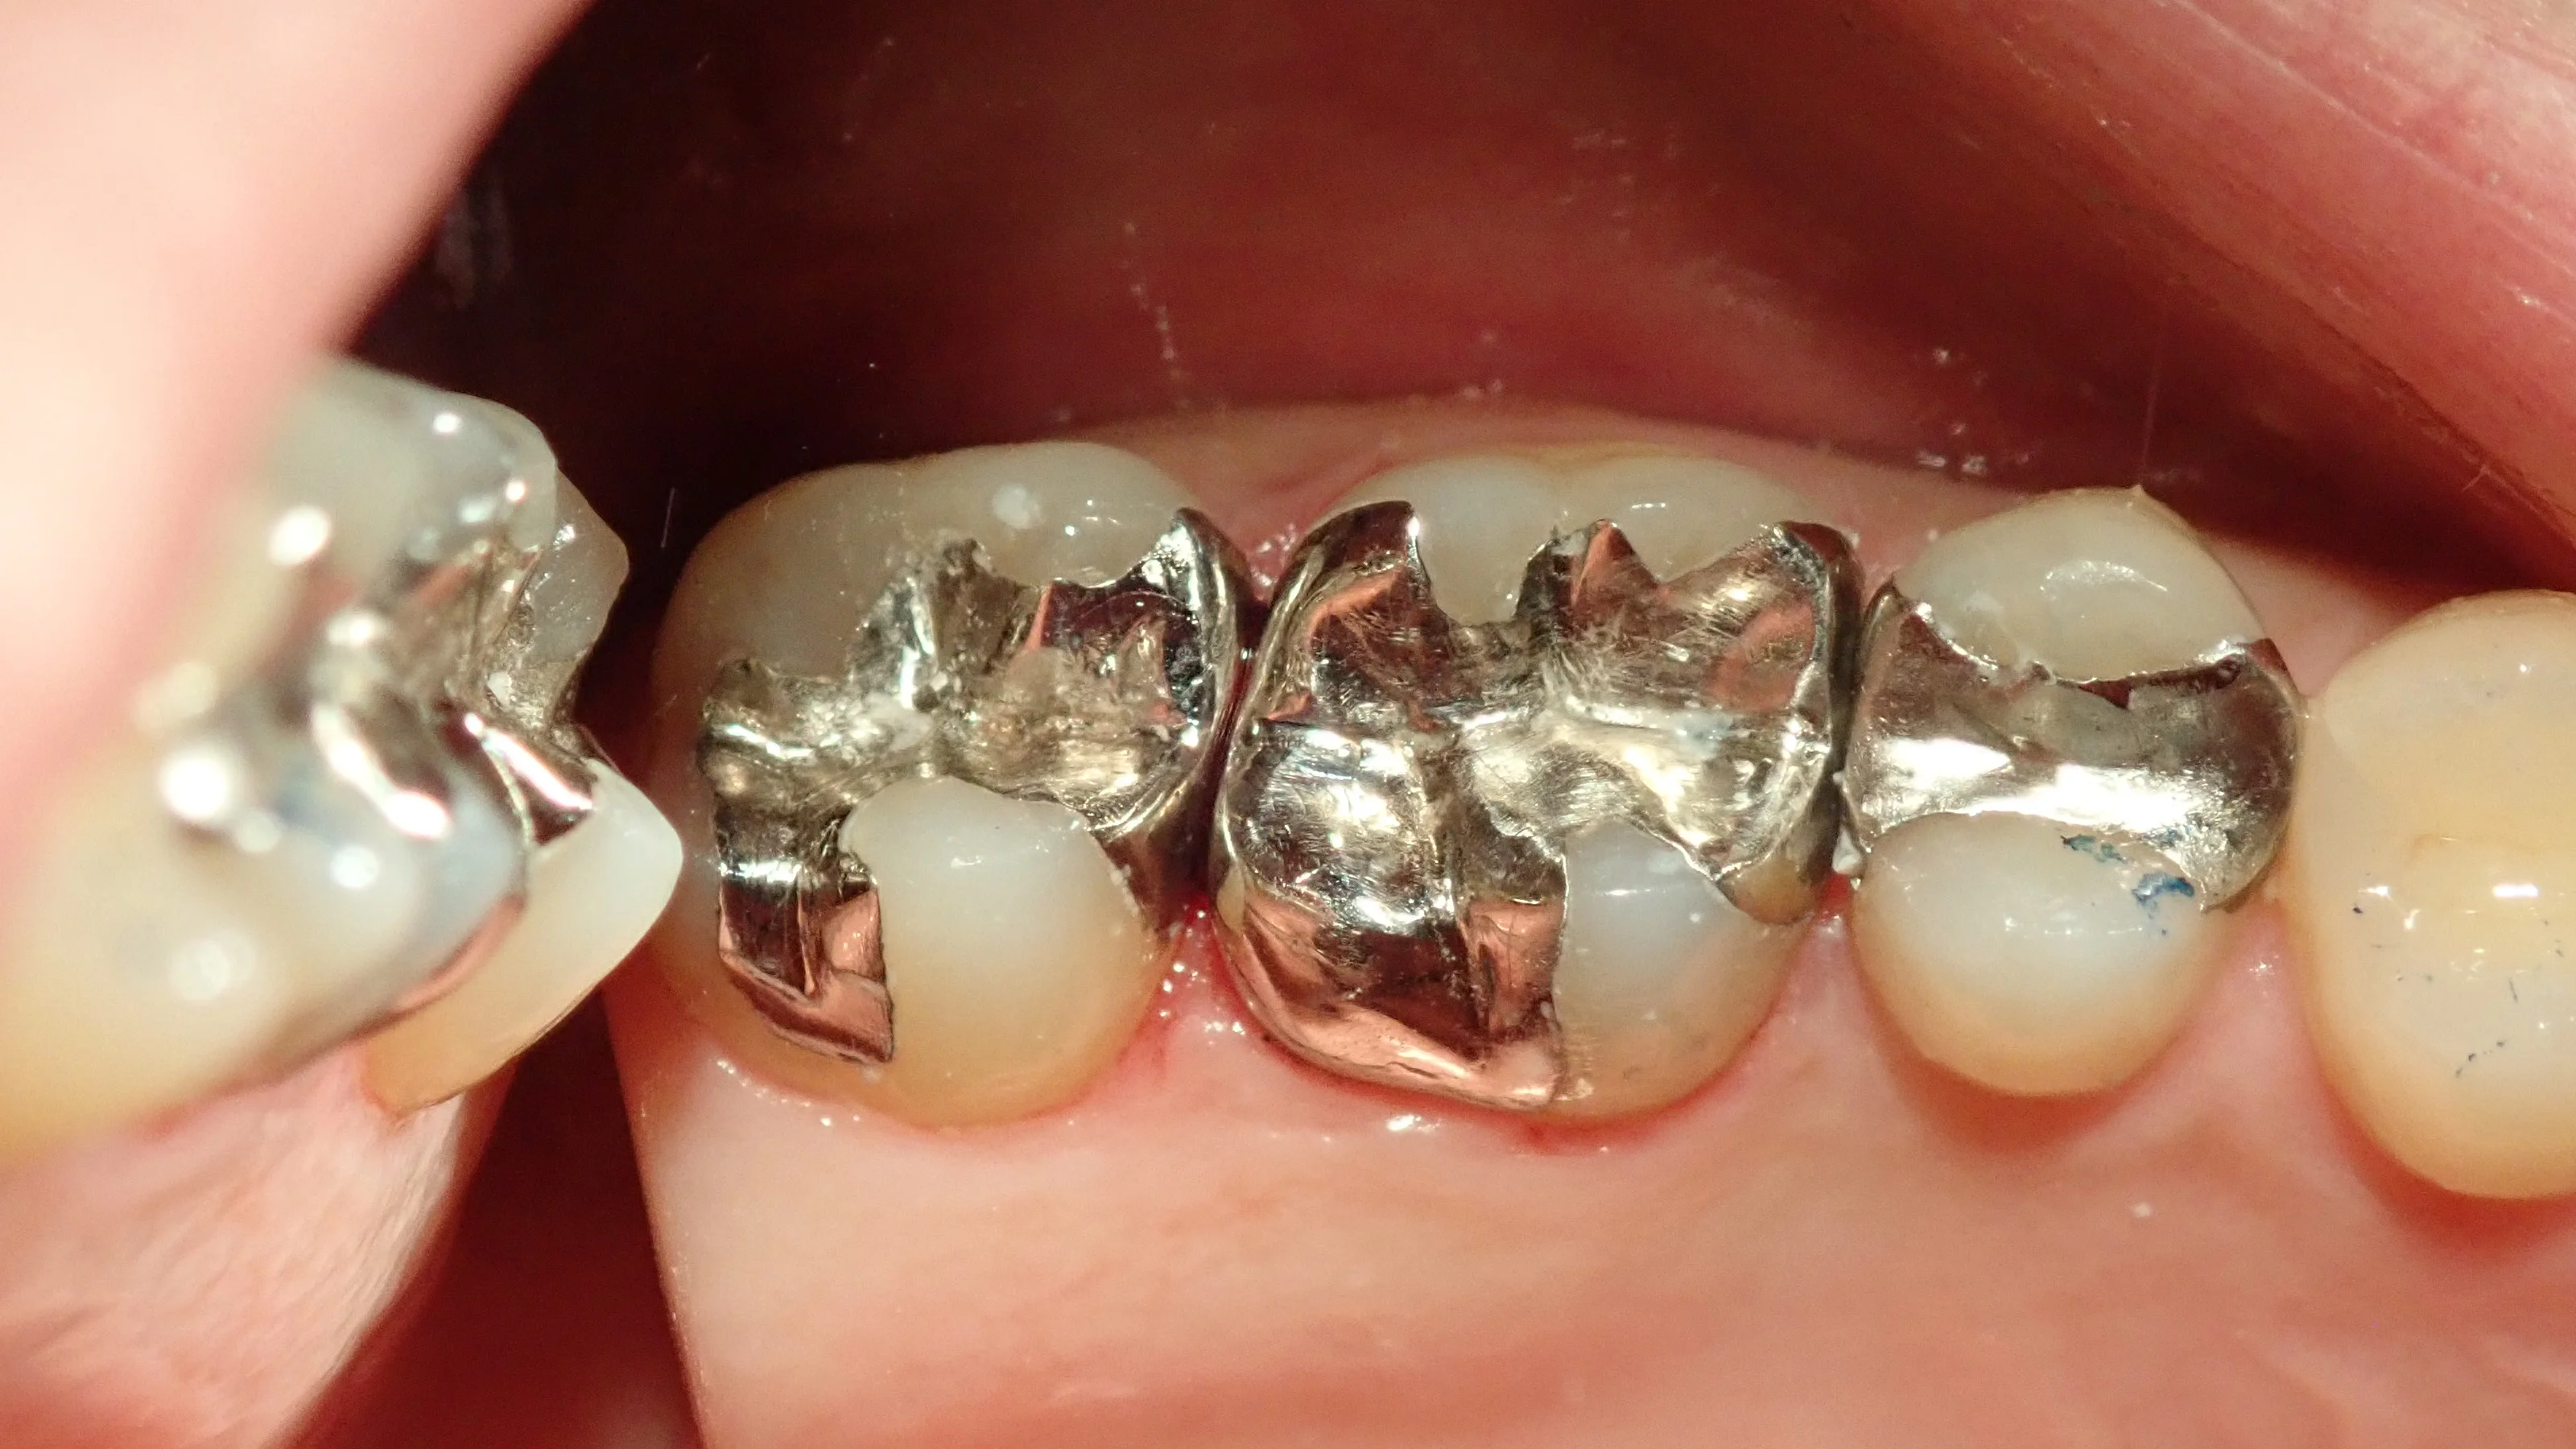

実際に装着したのがこちらです。

適合も良く、しっかりと入りました。

装着後しばらくは冷たいものや温かいものが染みるような感覚があったそうですが、だんだんと良くなったそうで、現在は全く問題は無いそうです。

※フライパンや車のボンネットで考えて貰うと分かりやすいですが、金属は熱を通しやすいです。

その為、一時的にですが冷たいものや温かいものが染みるような感覚が出ることがあります。